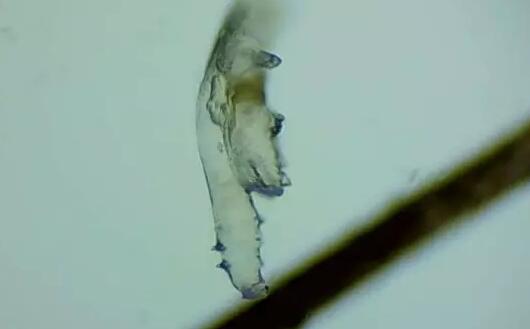

蠕形螨性睑缘炎

随着年龄增长,眼睛寄生有蠕形螨的几率也会逐渐增加,60、70岁左右的人群感染螨虫的几率更是接近99%。蠕形螨会引起蠕形螨性睑缘炎,患者会出现眼痒、异物感、眼干、睑缘充血、鳞屑、睫毛根部袖套状分泌物及睫毛脱落等典型表现,严重者可并发结膜及角膜病变。